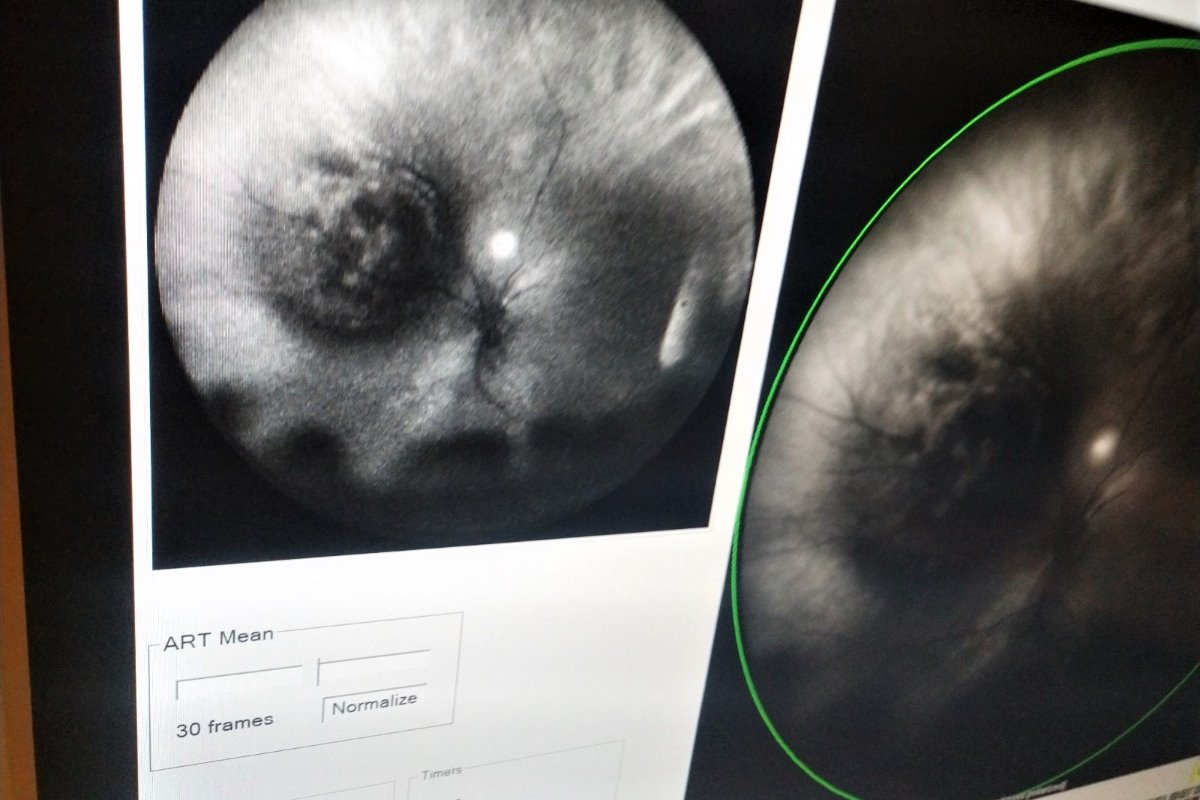

For the past six months, Deprise has been experiencing problems with her eye and even began to lose partial vision. My sweet 25 year old daughter was recently diagnosed with Ocular Melanoma in her left eye. This eye cancer is potentially lethal - especially if it spreads to her liver, and the doctors hadn't discovered the choroidal tumor until last month. We've learned there were "markers" that were signs that Deprise could have eye cancer. Since birth, she's had a beautiful dark spot in the brown area of her iris. We didn't think much of this, but we thought it was cool and interesting. Our family talked about it over the years and were mystified by it. This week her eye surgeon, Dr. Arun D. Singh, told her he immediately recognized another marker for potential cancer- a faint green color in the skin of her upper eyelid. Sadly, we couldn't have known these were signs of possible eye cancer.

Thankfully, surgery is taking place soon! Radioactive seeds are attached to one side of a disc and sewn directly on the outside wall of the eye near the tumor. It aims radiation at the tumor and it will continuously administer concentrated radiation to thetumor and hopefully destroy it. If it isn't stopped now, it may go to her liver, and then follow to her other organs like the lungs, bones and brain. The surgery is so important to her health and even her survival. The surgery is not guaranteed to completely destroy the tumor, and there is a possibility of her losing her eyesight completely in the affected eye.